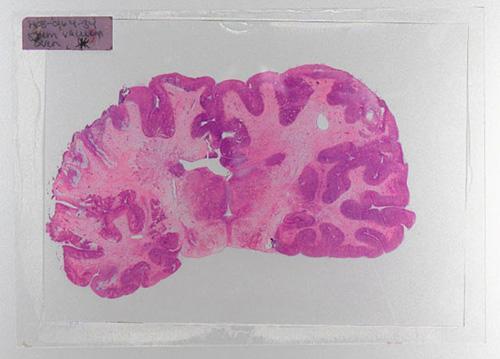

以前科学家分析髓鞘分布只能通过尸体解剖,将大脑取出切片。(图)

以前研究髓鞘分布细微差异的唯一途径是尸体解剖,将大脑取出切片,然后对髓磷脂染色分析。新方法将当前的两种磁共振成像(MRI)扫描技术结合起来,利用扫描数据来绘制脑中的髓磷脂分布图,用不同颜色代表髓鞘分布密度水平,如红色和黄色表示髓磷脂含量高的区域,蓝色、紫色和黑色表示含量水平较低,定位更加精确迅速,通过MRI扫描10分钟内就能得到数据。